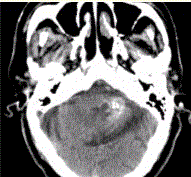

问题 男性,80岁,左耳听力下降伴头晕半年。头CT显示如下图。 需与海绵状血管瘤鉴别的病变包括

选项 A.弥漫性轴索损伤 B.高血压性微出血 C.血管淀粉样变 D.毛细血管扩张症 E.AVM F.成胶质细胞瘤伴出血 G.钙化性肿瘤,如少枝胶质细胞瘤

答案 ABCDEFG

解析 ABCDEFG